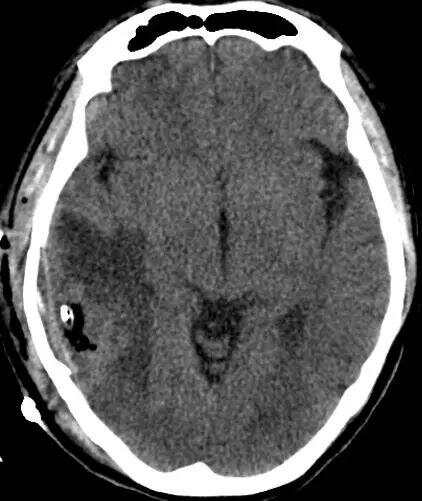

53歲的張先生以“突發(fā)意識不清4小時”代訴入院。入院時患者淺昏迷,極度煩躁。頭顱CTMRI提示:右顳葉占位病變伴出血,病灶呈不均勻強化,中心囊變,考慮高級別膠質(zhì)瘤。

術后CT